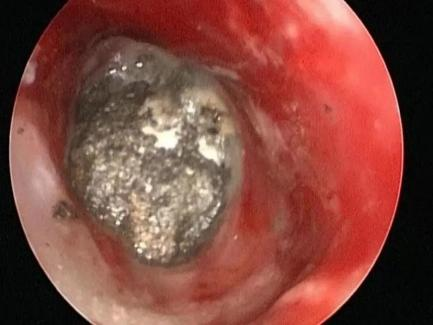

第二天,耳鼻喉科团队为患儿行急诊手术。在行气管插管全麻后,由副主任医师张金平在旁指导、主治医师谢记发主刀下,通过耳内镜下观察,见外耳道深部一不规则石头,已进入鼓室腔,完全阻塞鼓室内结构,外耳道黏膜部分缺损,外耳道骨质裸露,碰触石头,见缝隙处有少量脓液溢出。

耳内镜下初步对异物情况进行判断,不可能直接取出。遂启动第二方案,微创行耳内切口,扩大术腔,磨除外耳道骨质,扩大外耳道。因石头棱角较多,主刀医生边松动石头边磨除棱角处骨质,小心旋转角度,向外用力终于取出约6.6mm×4.3mm的异物。